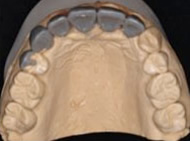

患者様の上下の歯列を方取りし、出来上がった模型を咬合器と呼ばれる器械に付着し、咬み合わせをチェックします。噛み合わせが悪いままでインプラント治療を行なっても失敗に終わります。また、この診査は顎の関節や天然の歯の将来性を診る上でも非常に重要といえます。